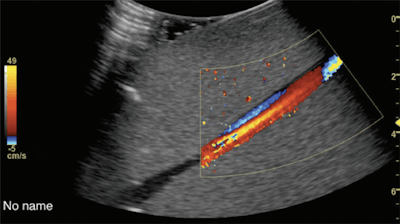

Researchers from across the U.S. confirmed the efficacy of 3D color-flow ultrasound for cheaply and reliably measuring blood flow. The findings, which were published on June 30 in Radiology, could help physicians precisely measure blood flow for people with chronic conditions.

Kripfgans and his colleagues at Michigan Medicine had previously developed a 3D color-flow ultrasound approach to overcome the limitations of alternative measurement solutions. The researchers tested the method in the new, prospective study, which received funding from the U.S. National Institutes of Health, RSNA, and the American Institute of Ultrasound in Medicine.

The use of 3D color-flow ultrasound produced measurements that were accurate and reproducible. Two out of the three ultrasound systems tracked within 10% for measuring flow response, the authors noted.

The approach is promising because it requires no hardware changes and can lead to practical clinical uses for measuring peripheral vascular flow and cerebral blood flow. While it will need to be further evaluated and may not work for all types of blood flow measurements, Kripfgans is optimistic about its clinical potential.